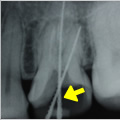

抜髄症例

主訴:3日前から何もしなくても前歯が痛む

- 虫歯が大きく神経まで達している為、虫歯を除去し抜髄

- ファイルを使って根の長さを測定・根管形成(根管-神経が入っていた管-を根管充填しやすい形に整えること)

- 根管充填剤が根尖(根の先端)まできっちりと充填